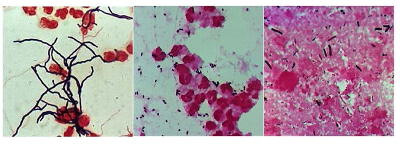

What are acid- fast stains used for?

To identify acid fast genetically engineered bacteria (mycobacteria). Hot pink. Grow inside macrophages so tend to grow in clumps (hundreds of organisms in a clump)

Bacillus anthracis

Streptococcus agalactiae